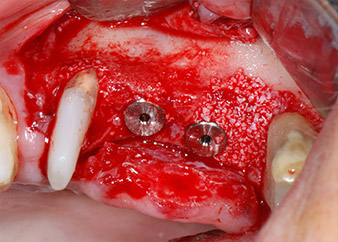

Gli impianti (Restore, Keystone Dental,, diametro 3,75 mm, lunghezza 8,0 mm) sono stati posizionati con il motore per impianto (Figg. 11 e 12).

pronto per le viti di copertura

Fig. 12: Entrambi gli impianti sono posizionati e pronti per le viti di copertura.